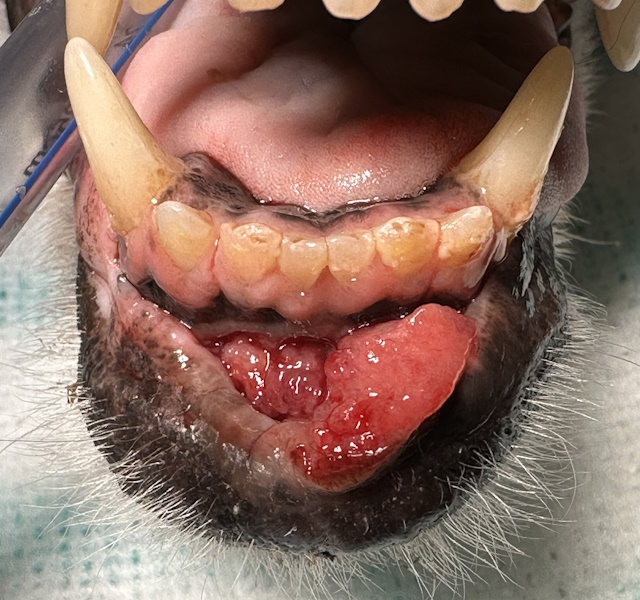

Ulcerative and bleeding growth under the tongue. Biopsy revealed a sublingual squamous cell carcinoma.

Hyperplastic, ulcerative and bleeding lesion in the caudal mucosa and mandible. Biopsy showed squamous cell carcinoma.